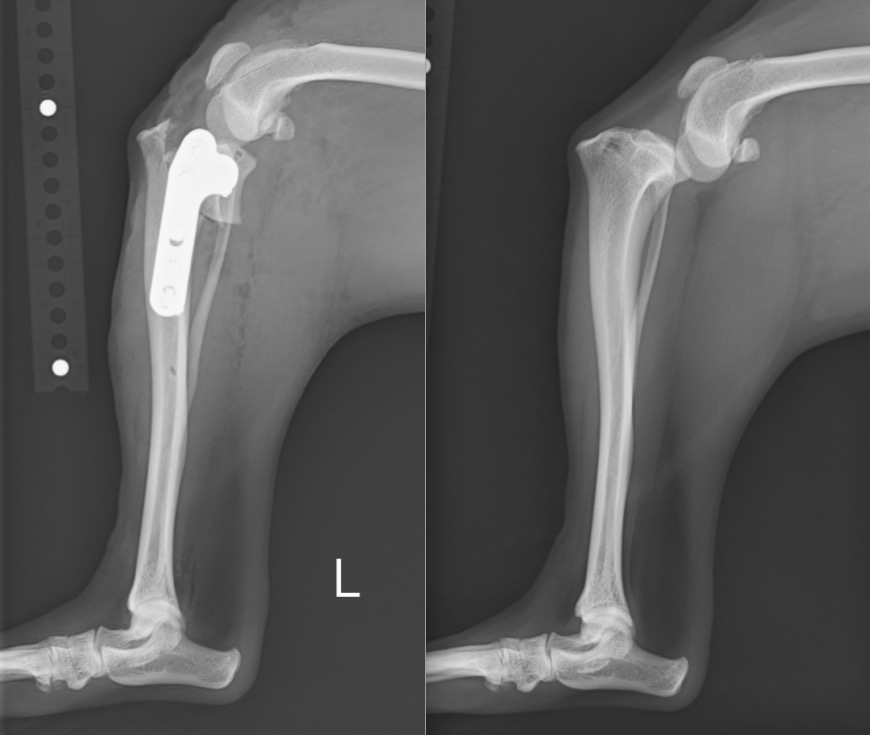

本症例は膝蓋骨内方脱臼に対する手術を行い脱臼を整復すると同時に、前十字靭帯損傷による膝の不安定性に対しTPLO(Tibial Plateau Leveling Osteotomy:脛骨高平部水平化骨切術)を実施しました。

手術前と手術後のX線写真を比べると、膝のズレが解消し、お皿の骨も真ん中に整復されていることが分かるかと思います。

左:術後 / 右:術前